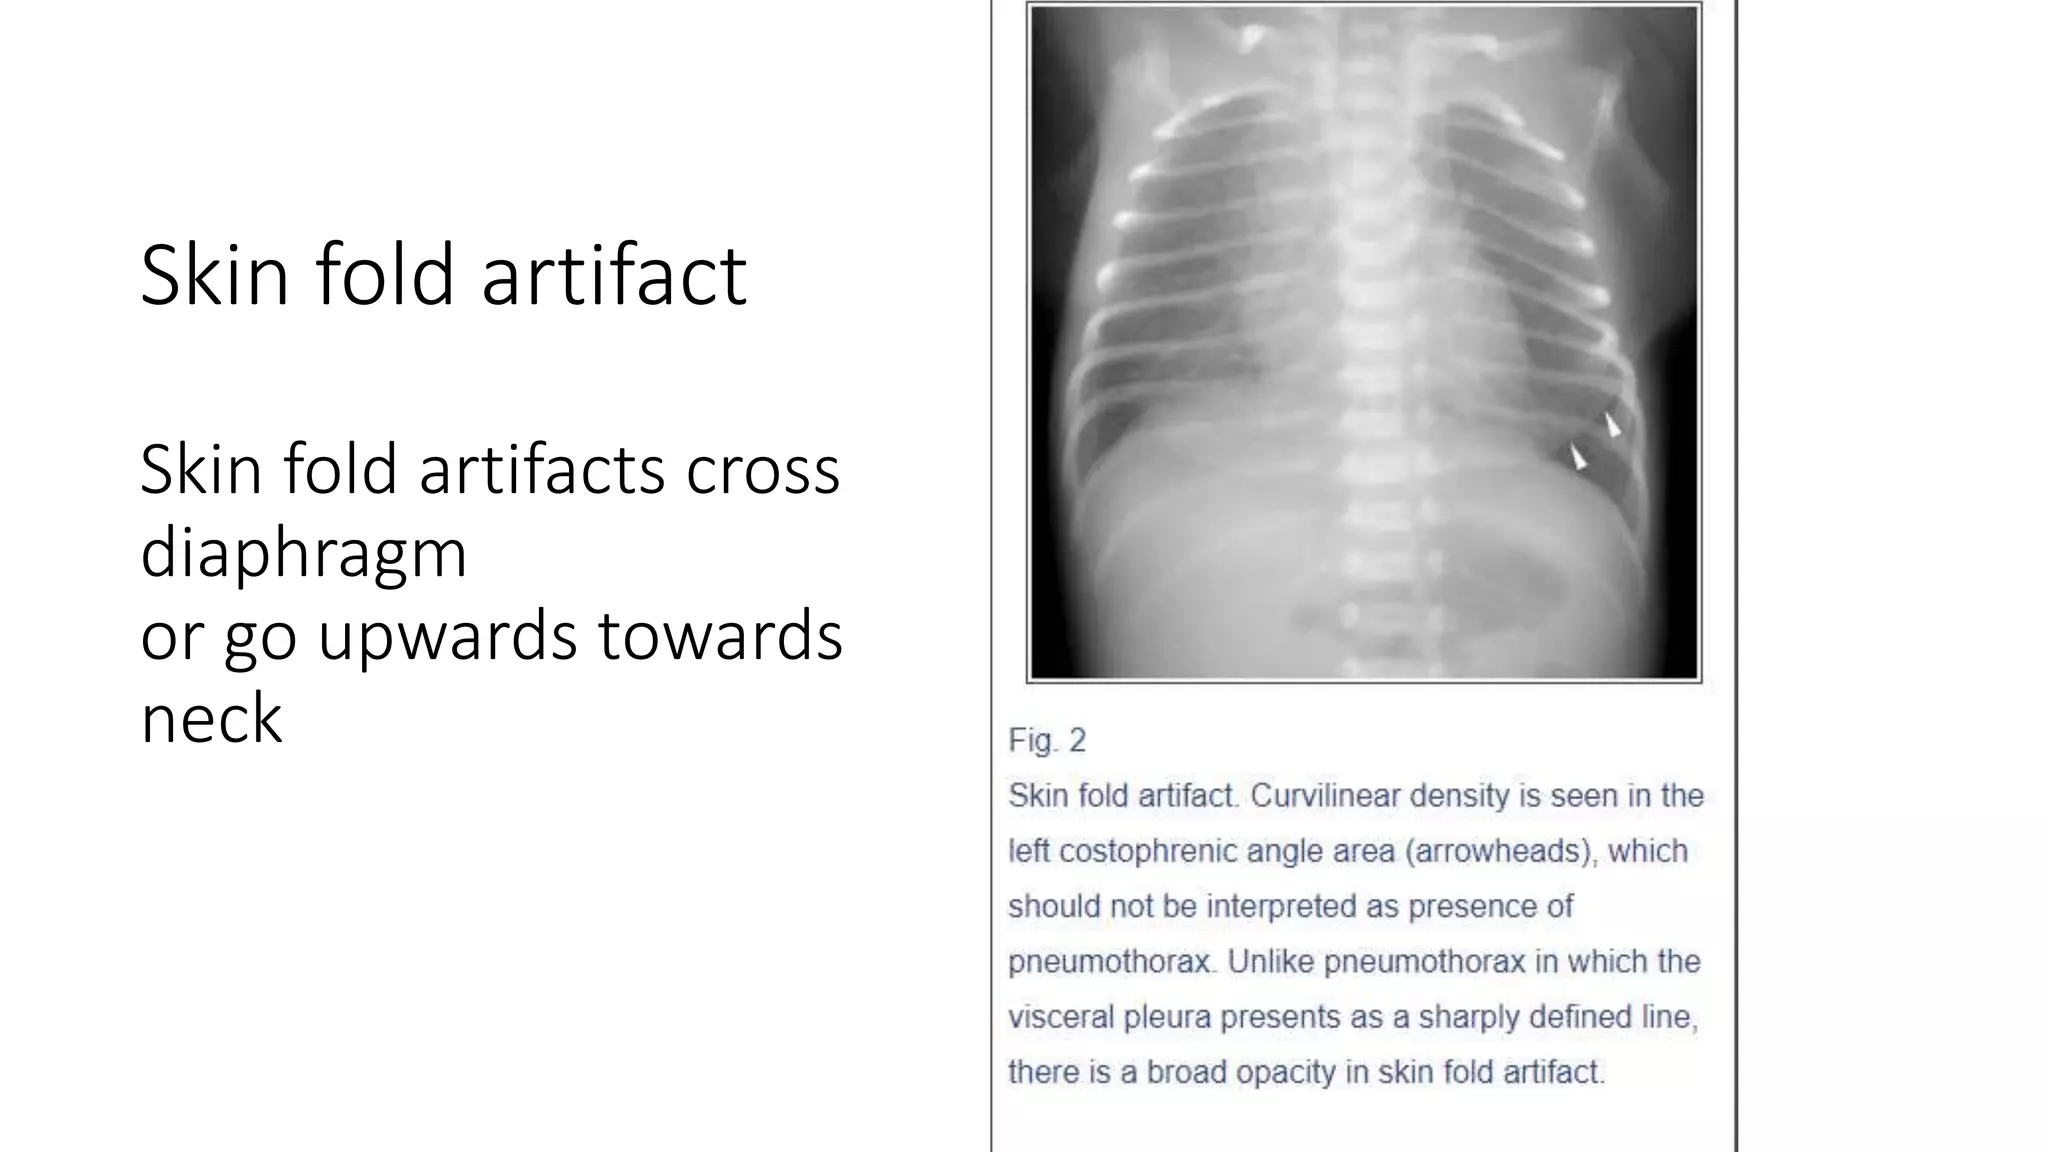

This document provides an overview of neonatal chest x-rays, including when they should and should not be performed, what a normal x-ray looks like, common positions of tubes and catheters, and common causes of respiratory distress in neonates. It discusses the appearance of a normal chest x-ray as well as conditions like respiratory distress syndrome, transient tachypnea of the newborn, meconium aspiration syndrome, and pneumonia. Surgical conditions like diaphragmatic hernia and esophageal atresia are also reviewed.